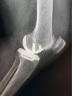

微创单髁置换手术就是微创保膝理念的有效解决办法之一。它也叫做部分膝关节置换术,手术只是将膝关节内侧部分磨坏的股骨和胫骨骨头切除,装上非常耐磨的人工材料,保留外侧未磨损的关节和关节内所有韧带。而且手术可以通过比全膝置换小得多的伤口来完成,其创伤小、出血少、恢复快、假体寿命长、功能恢复程度高等一系列优点正逐步的显示在世人眼前。

宣武医院骨科关节组在曹光磊主任的带领下,正在以微创保膝为理念,阶梯化治疗膝关节骨关节炎。目前宣武医院骨科关节组是北京最早开展保膝化治疗的团队之一,通过细致的体格检查、规范的影像学检查和术中证实,严格把握患者的手术适应症,将众多“前内侧骨关节炎”的患者寻找出来,选择微创单髁置换术,取得了很好的效果。